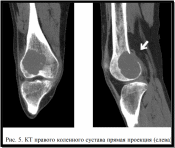

Диагностика: В первом этапе диагностики при подозрении на опухоль кости выполняются общепринятые обзорная и прицельная рентгенография пораженной области с близлежащим суставом. Компьютерная томография [КТ] и магнитно-резонансная томография [МРТ] позволяют более точно определить структуру кортикального слоя и мягкотканного компонента.

По данным рентгенологических методов исследования ГКОК проявляется зоной остеолитической деструкции с четкими, неровными контурами, которая в большинстве случаев расположена эксцентрично и может быть отграничена от неизмененной кости полосой (зоной) остеосклероза (рис. 5).

Для ГКОК характерны патогномоничные рентгенологические симптомы, такие как подрытие, истончение и «вздутие» (периостальная скорлупа) коркового слоя. Нередко встречается симптом «писчего пера» по краю опухоли.